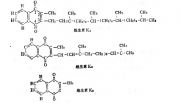

| 2021年7月26日 (一) 20:03 | 维生素K123.jpg (文件) |  |

39 KB | Uploaded with SimpleBatchUpload | 3 |